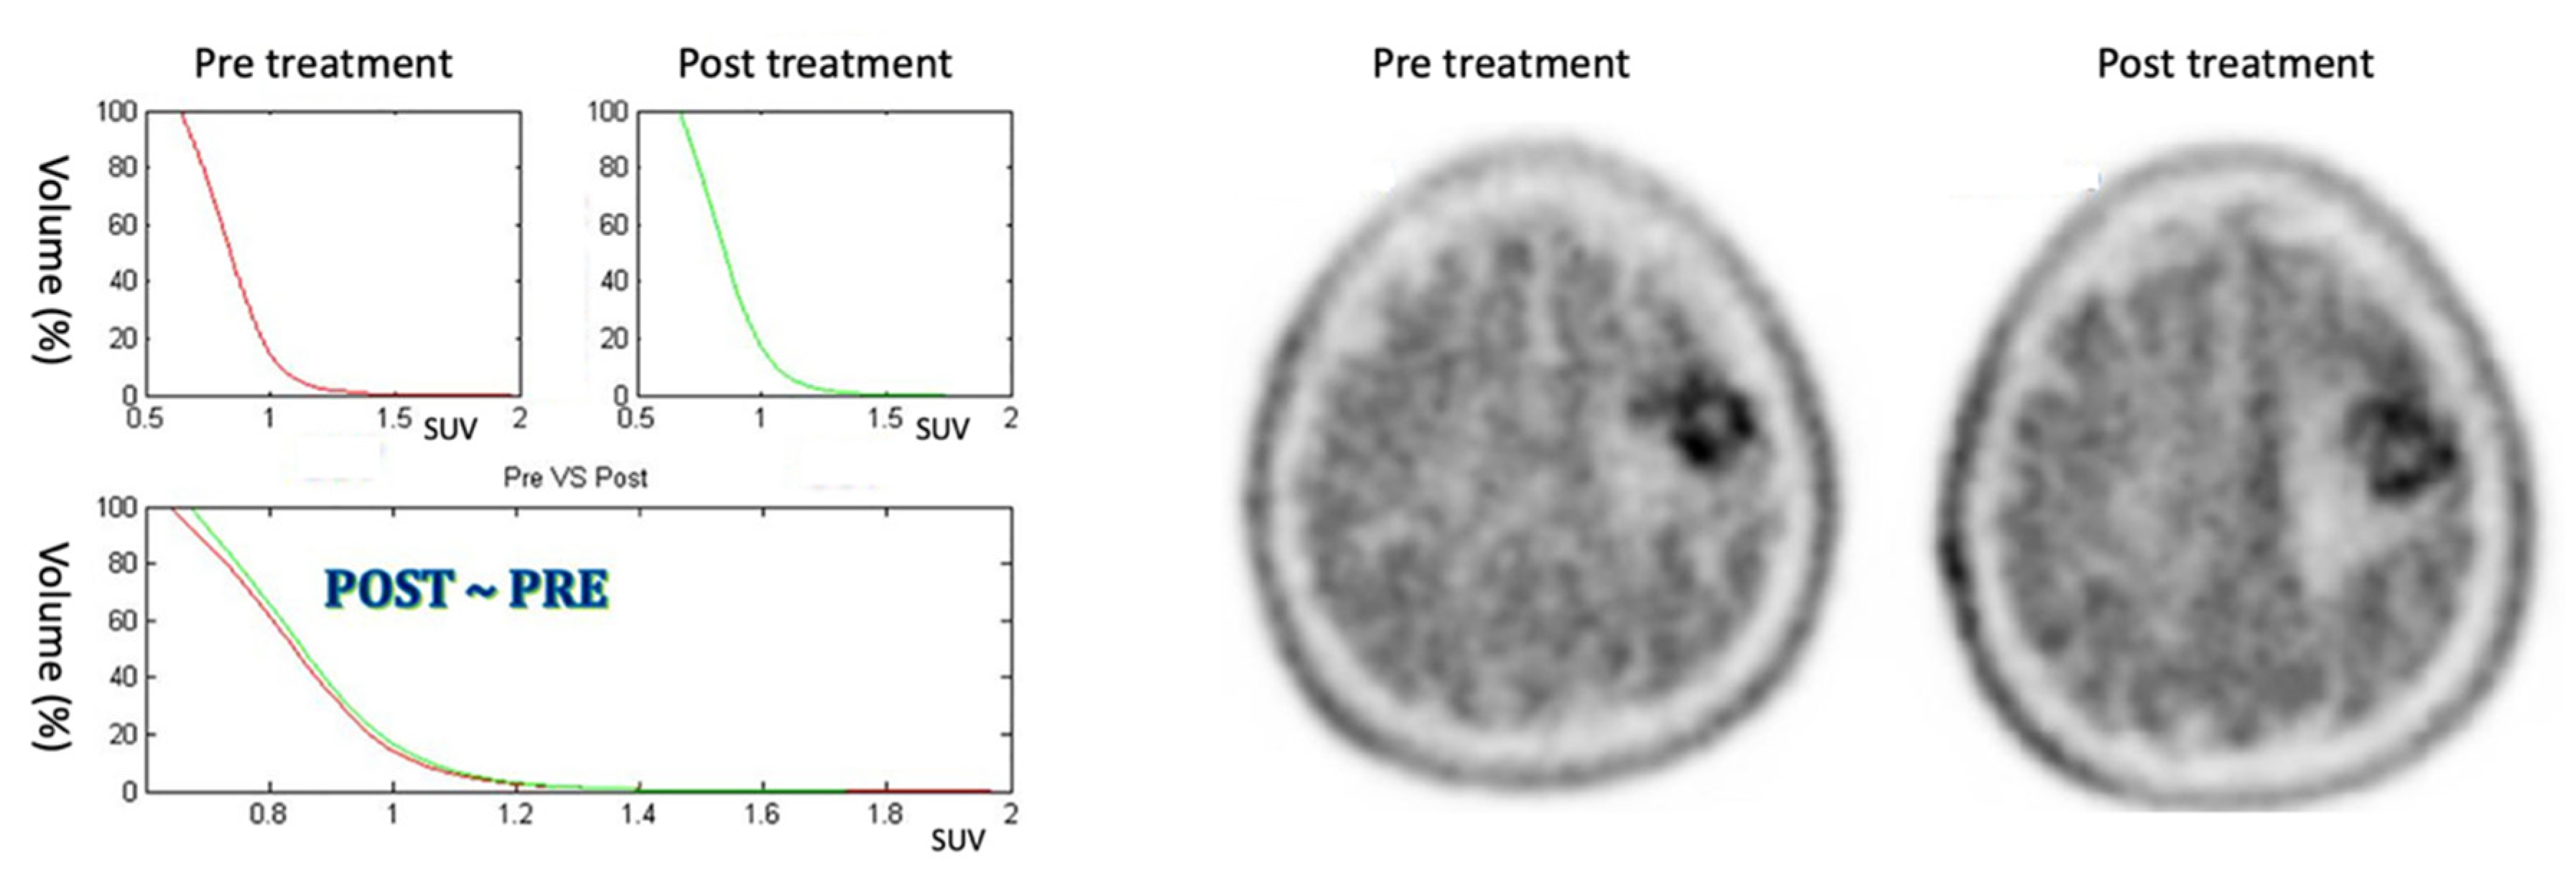

3.2. Stable Response

The five patients included in this class show a AUC reduction of less than 10% and no modification of the CSH between the PET pretreatment and the PET post-treatment, as it is possible to see in Figure 7 (patient #1). Patients included in this category show a moderate response to the therapy.

Figure 7.

On the left: CSH pretreatment (top left); CSH post-treatment (top right); comparison between pre- and post-treatment (bottom) in stable response case: ΔAUC = 2.33%. On the right: PET images of pre- and post-treatment. (For interpretation of the references in this figure legend in colour, the reader is referred to the web version of this article.)